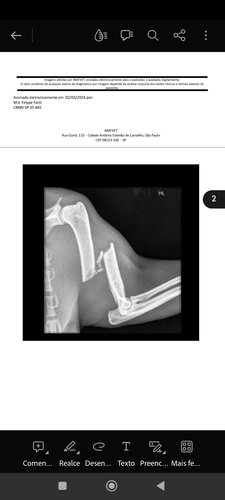

Sou um gatinho de aproximadamente 07 anos, vivo na rua a mais ou menos 1 ano pois meu antigo tutor se mudou e me deixou. Desde então a tia Érica e alguns tios na rua me alimentam, porém estou com a osso da patinha esquerda quebrado, e para piorar saiu a biópcia nesta mesma pata que está inchada que fiz e o laudo mostrou que o inchaço é um carcinoma onde o osso está quebrado, além de fazer a cirurgia tudo indica que terei que amputar minha pata. Estava tudo certo desde o dia 02 de março para eu ficar na casa da tia Érica, meu hemograma está top, embora preciso urgente da cirurgia, porém ao fazer o teste de FIV e FELV, deu positivo para FELV, sou assintomático e não apresento os síntomas, porém a tia Érica tem 08 gatinhos que não são vacinados e sua casa tem somente 03 cômodos e não tem um local separado para eu ficar por conta da Felv. Ajudem nesta vakinha pessoal, pois além de fazer a cirurgia vou precisar de um lar pois tudo indica que vou amputar a pata e não poderei mais viver nas ruas, ainda mais sendo Felv positivo, a cada dia que se passa a cirurgia fica mais longe com a demora das doações, a Felv pode fazer eu piorar e posso não resistir mais, sem contar que fico mancando da pata na rua, me ajudem a bater a meta dessa cirurgia, me ajudem a conseguir um lar e ter uma vida digna mesmo que não seja por muito tempo